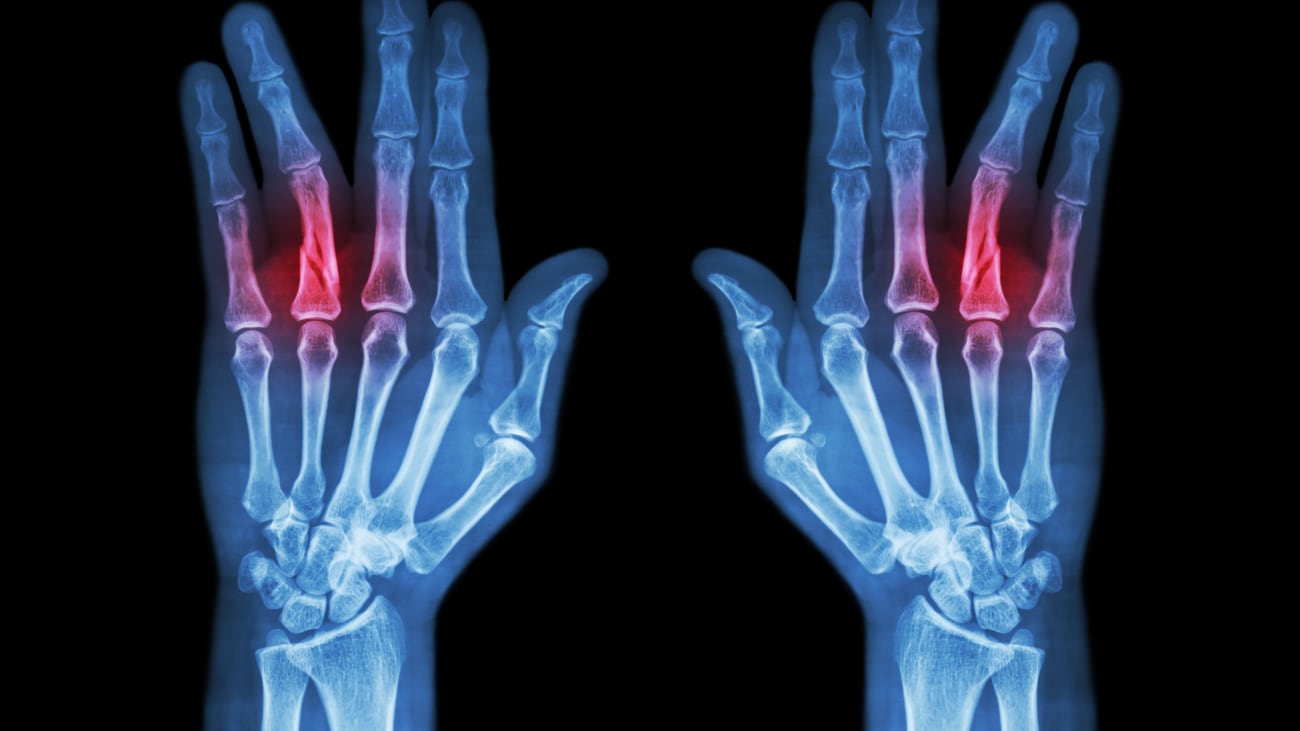

Hand Pain and Rheumatoid Arthritis Fingers Hurt Daily This article walks you through the various treatment options for finger arthritis and how each can help. Hand pain can result from injury, arthritis, and other health conditions, including autoimmune disease. Opening jars, closing doors, tying shoes — these are just a few things we need our fingers to. Your symptoms might also give you an idea of what's causing. Fingers Hurt Daily.